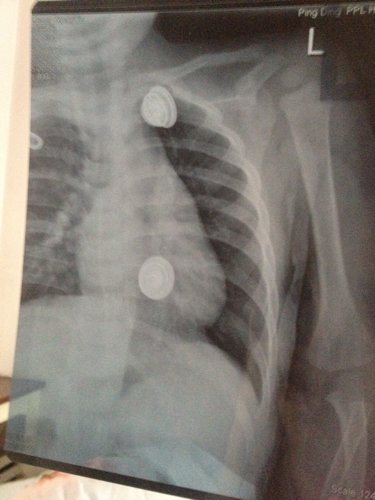

一岁半宝宝从写字台上掉下'诊断结果为左锁骨中段青枝骨折 请问'愈合需要多长时间'需注意什么 会不会

病情分析: 您好,根据您提供的情况看,您的宝宝一岁半了,现在锁骨骨折了,但骨折程度较轻,属于青枝骨折。 指导意见: 小孩子骨折愈合快,无需特殊的饮食及药物治疗,一般在1个月左右就可以愈合了。骨折愈合后不会留下后遗症的,不用担心。